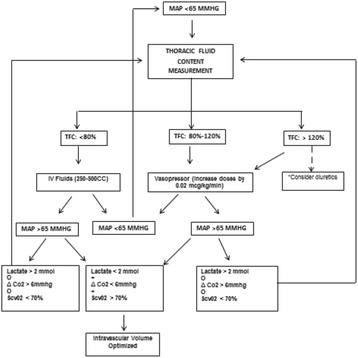

P198 - An ultrasound- guided algorithm for the management of oliguria in severe sepsis

I. Hussain, N. Salahuddin, A. Nadeem, K. Ghorab, K. Maghrabi